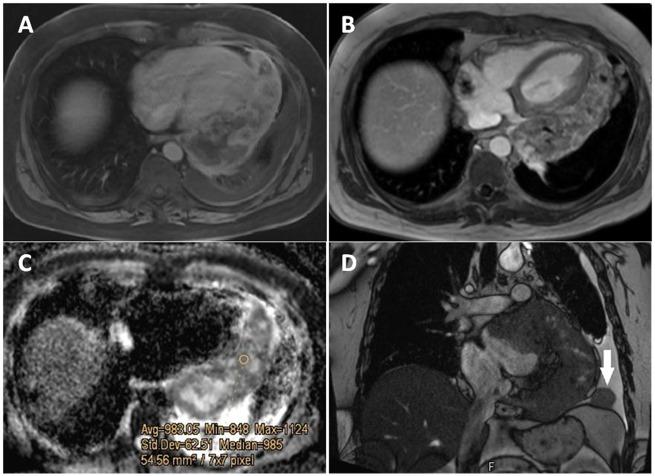

Primary pericardial mesothelioma is a rare primary cardiac malignancy, with three main histopathological types, sarcomatoid histotype being the rarest. The imaging features were atypical due to concomitant extensive calcification, which resulted in aggravated differential diagnosis.

A 45-year-old man presented to our hospital with non-specific clinical symptoms. According to clinical history, a mediastinal tumour had been suspected with a previous unsuccessful attempt of transthoracic computed tomography-guided biopsy at an overseas hospital with limited data of performed imaging procedures. Multimodality imaging at our centre revealed extensively calcified solid masses in the pericardium, invading the left atrium. As the imaging features suggested an atypical primary pericardial malignancy, a diagnostic thoracoscopy was performed. Histopathological analysis of specimen revealed sarcomatoid type of pericardial mesothelioma with areas of necrosis and foci of osteogenic differentiation. Despite planned treatment, 2 weeks after histological diagnosis, the patient passed away due to perforated peptic ulcer-related sepsis.

The presence of extensive calcification in the lesion resulted in a challenging imaging workup and diagnosis. Initial differential diagnosis included primary or metastatic calcification-prone tumour, secondary calcification due to haemorrhage after previous interventional procedure and other pathologies, such as tuberculous pericarditis, calcified amorphous tumour, among others. Calcification may be part of the histological tumour characteristics; however, proper history taking is crucial as concomitant diseases, previous treatment, and interventional procedures may alter the imaging pattern.